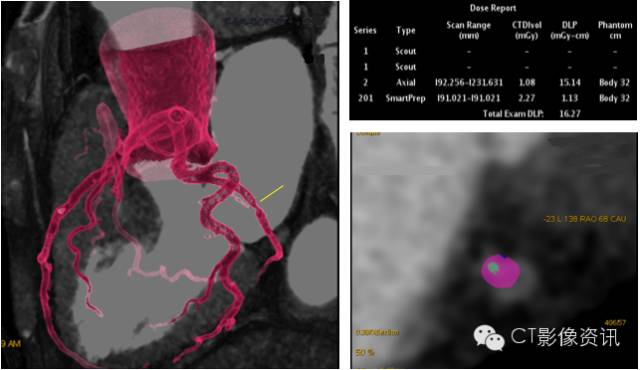

Case 4 男性,63岁,支架术后复查。

扫描协议 探测器宽度:120mm, Axial; 管电压和管电流:70kV, Smart mA; 旋转速度:0.28s/rot ;迭代:ASiR-V 50%;体重指数:23.4; 对比剂:270mgI/ml, 25ml, 4.2ml/s; 扫描剂量:0.166mSv。

点评 冠脉支架植入是治疗冠心病冠脉狭窄的主要方法之一。Revolution CT 使用了宝石探测器、视网膜集成化数据采集系统,全新的HD 高清扫描模式,实现了0.23mm的可视空间分辨率, 最新的ASiR-V 迭代重建平台,能较好的显示支架腔内的情况,并对整个冠脉及支架做出精确评估。

迭代重建算法已经成为现代CT降低辐射剂量的重要方法。Revolution CT 采用了更为先进的ASiR-V全模型实时迭代平台, 与以往的迭代算法相比,具有更为先进的系统噪声模型、被扫描物体模型和物理模型。其优点表现在降低噪声、扫描剂量下降、密度及空间分辨率提升,以及减轻伪影。